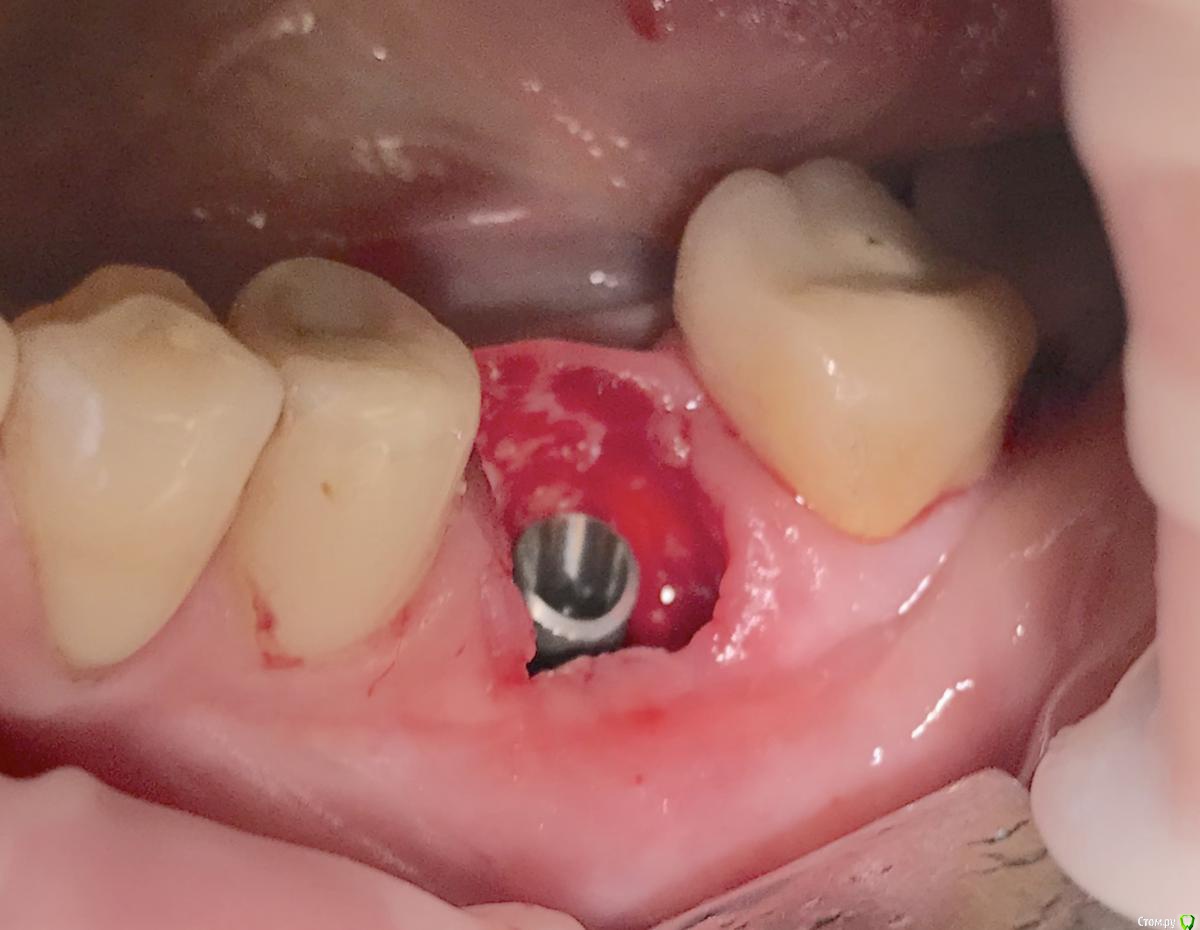

колесников Опубликовано 22 апреля, 2019 Поделиться Опубликовано 22 апреля, 2019 (изменено) И снова профайл спасает жизнь (облегчает жизнь имплантолога)Стандартная ситуация:36 периодонтит в стадии обострения с грануляциями,эксудацией,резорбцией компактной пластинки,дефицитом прикреплённой слизистой вестибулярного. Одна хирургия. Ноябрь 2018. Удаление,кюретаж,имплант Astra tech profile 4.5x9 под заглушку,торк около нуля. Вестибулярного сст,консервация графтом Sureoss 0,5 чипс с APRF,закрытие шайбой по Ноймайеру. Через неделю шайба несостоятельна-удалена. Пациентка созрела на удаление 37го. Выполнена декоронация в связи с отъездом пациентки,далее через 2 недели удаление и имплантация 37го. Промежуточный осмотр в январе. В марте установлены формирователи . Апрель контрольный осмотр. Периотест -5. Направлена на протезирование. Изменено 22 апреля, 2019 пользователем колесников 4 Ссылка на комментарий

колесников Опубликовано 23 апреля, 2019 Автор Поделиться Опубликовано 23 апреля, 2019 Разница от платформы до зенита 3 мм.Ещё раз. Вестибулярно дефект 9мм. Полное отсутсвие прикреплённой слизистой,язычное поднутрение и воспалительный процесс. Чтобы провести олномоментную имплантацию пришлось бы взять короткий имплант,заглубить его на 8мм от зенита,засыпать графтом,перекрыть мембраной,натянуть щеку и ждать-молиться чтобы края не разошлись и все не стухло. А после 2 -3 десневые пластики и глубокая шахта. Господа! Коллеги! Где сроки? Где бюджет? Где прогнозы? Ладно имплант и его глубина, это не так существенно,я вам показал как из ничего за 1 визит получить кератинизированую и прикрепленную слизистую без основания Ссылка на комментарий